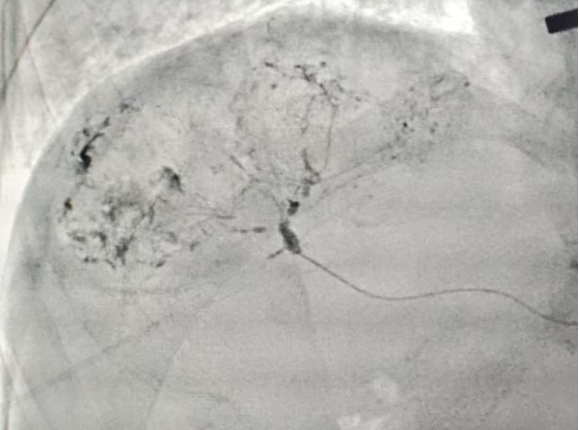

近日,我院介入治疗科董剑群主任团队为多名肝癌患者实施了无鞘微导管介入治疗,这标志着我院在微创介入诊疗领域正式迈入“微创中的微创”新阶段,为临汾地区的患者带来了更安全、更舒适的治疗新选择。

传统介入手术需要通过直径约2.1mm(5F)的血管鞘建立治疗通路,不仅穿刺创口相对较大,患者术后需卧床制动12—24小时,卧床周期长。而无鞘微导管技术彻底摆脱了传统血管鞘的“束缚”,医生以“穿针引线”般的精准操作,将直径仅0.5mm—0.86mm(1.9F-2.6F)的微导管借助导丝送入患者血管,最终精准抵达病灶位置。

这项技术的“极致微创”优势包括:穿刺入口直径不到0.9mm,和日常静脉输液的套管针大小相近,血管穿刺入口面积相比传统技术减少83%以上,大幅降低了血管损伤风险与术后并发症概率。手术多采用桡动脉(手腕)或肱动脉(肘部)等上肢入路,患者术后无需卧床。穿刺点仅需压迫止血2小时左右即可拆除绷带。不少患者术后能自行走下手术台,“走着回病房”已经成为常态,彻底打破了介入治疗“术后必卧床”的固有印象。极小的穿刺创伤让肱动脉具备极佳的可重复性,为需要多疗程治疗的患者搭建起了安全可持续的“生命通道”。

我院介入治疗科董剑群主任团队此前就持续探索并开展上肢桡入路外周介入治疗,此次将无鞘微导管技术引进医院,并逐步拓展到其他实体肿瘤灌注化疗及栓塞、出血性疾病治疗等领域,让“极致微创”惠及更多临汾患者。